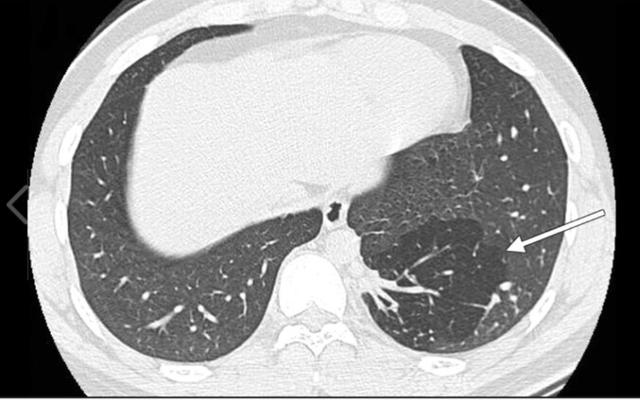

Hình ảnh chụp cho thấy có một thuỳ phổi biệt lập bên phổi trái của bà C

Tháng 10/ 2018 bà đã điều trị một đợt tại bệnh viện khác, sau khi chụp phim cắt lớp vi tính lồng ngực thì phát hiện có một thùy phổi biệt lập bên phổi trái. Bác sĩ chỉ định phẫu thuật cắt bỏ thùy phổi biệt lập này.